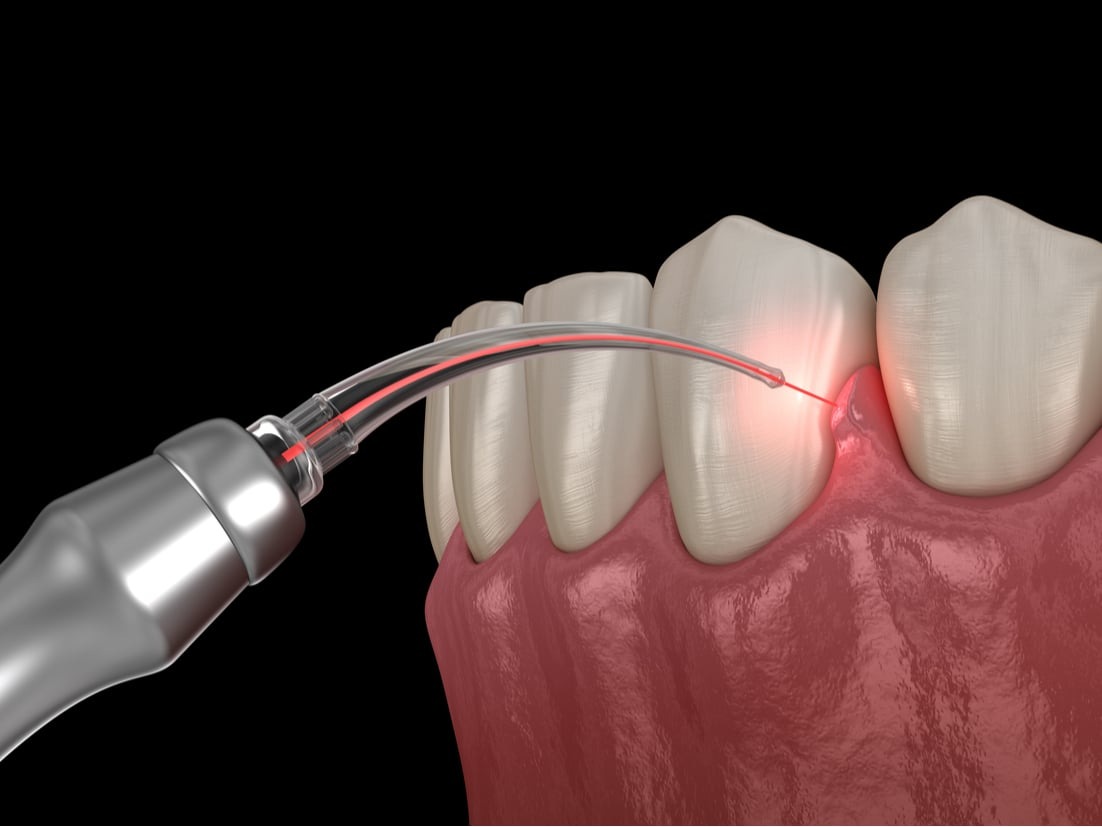

LANAP® (Laser Assisted New Attachment Procedure) is an FDA-cleared laser treatment used to treat moderate to severe periodontal (gum) disease without traditional surgery.

Instead of cutting the gums with a scalpel, LANAP uses a specialized dental laser to:

- Remove infected gum tissue

- Kill harmful bacteria

- Preserve healthy tissue

1. Laser Removal of Infection

A dental laser targets and removes diseased tissue and bacteria deep within the gum pockets.

3. Second Laser Pass

The laser is used again to stimulate clot formation and seal the pocket.